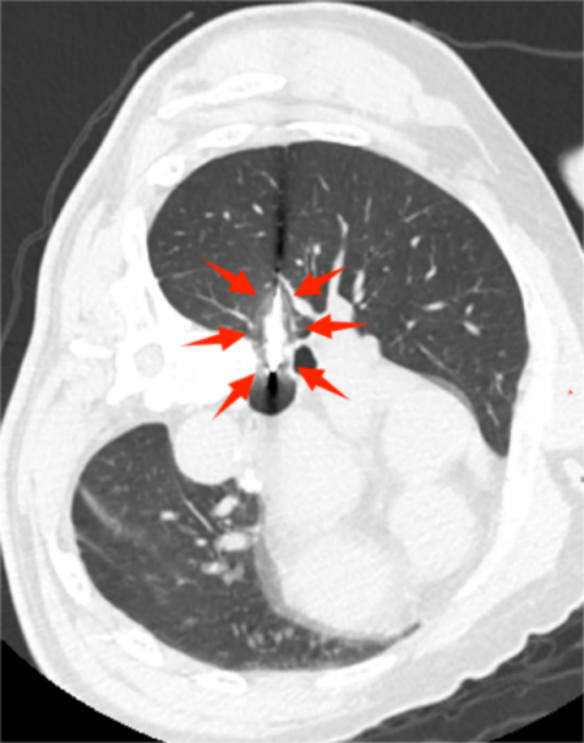

经历两次冰冻及解冻的冷热交替循环后,肺肿瘤及周围部分肺组织细胞发生不可逆的破裂坏死,同时破坏肿瘤的微血管,在CT上可见结节周围形成横径约2cm左右的冰球包裹肺结节。

△肺结节周围初步形成冷冻消融的界限

△形成横径约2cm左右的冰球包裹肺结节